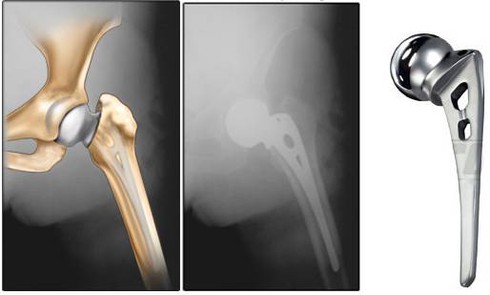

Hoại tử chỏm xương vô khuẩn là bệnh dễ nhầm với các bệnh lý khác |

Ông Đ hay bị đau khớp, nhất là lúc nửa đêm về sáng, nhưng ông cố chịu đựng. Khi không chịu đựng được nữa ông mới tìm đến bác sĩ thì bệnh đã ở giai đoạn muộn. Được biết, 4 năm trước bệnh nhân Đ. từng được thay khớp háng.

Đặc điểm của bệnh này là thường gặp ở vùng khớp háng nhiều hơn là vùng lồi cầu đùi. Cơ chế của bệnh là tiêu xương dưới bề mặt lớp sụn làm cho bề mặt sụn bị lún xuống, gây đau khiến bệnh nhân không đi lại được.

PGS Dũng cho hay, tại Việt Nam hoại tử xương vô khuẩn khớp háng, mà phải thay khớp háng hiện lên tới 60-70%, nên tỷ lệ bệnh nhân có nguy cơ bị hoại tử xương vô khuẩn khớp gối sẽ tăng cao. Với căn bệnh này, việc phát hiện và điều trị sớm mang lại hiệu quả hơn.